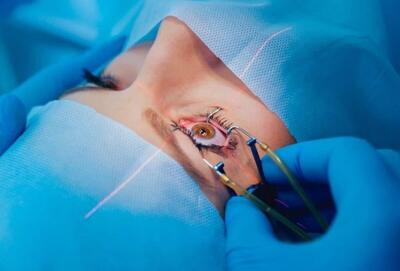

سپاه 120 کردستانی نیازمند را از نابینایی نجات داد- فیلم فیلم استان تسنیم | Tasnim

سازمان بسیج جامعه پزشکی سپاه بیتالمقدس استان کردستان 120 عمل جراحی و درمان آب مروارید چشم را به صورت رایگان در سنندج انجام شد. گزارش اختصاصی تسنیم را ببینید:

جراحی رایگان آب مروارید چشم توسط سپاه در سنندج - تسنیم

مسئول سازمان بسیج جامعه پزشکی استان کردستان گفت: به مناسبت سالگرد شهادت سردار حاج قاسم سلیمانی، جراحی آب مروارید چشم به صورت رایگان برای افراد نیازمند در سنندج انجام میشود.